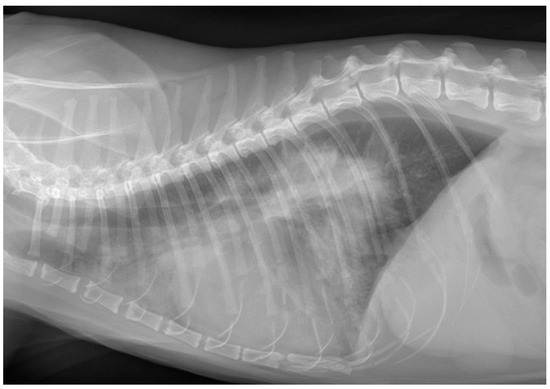

3.5. Results for the Cats in Group N—Neoplastic Origin